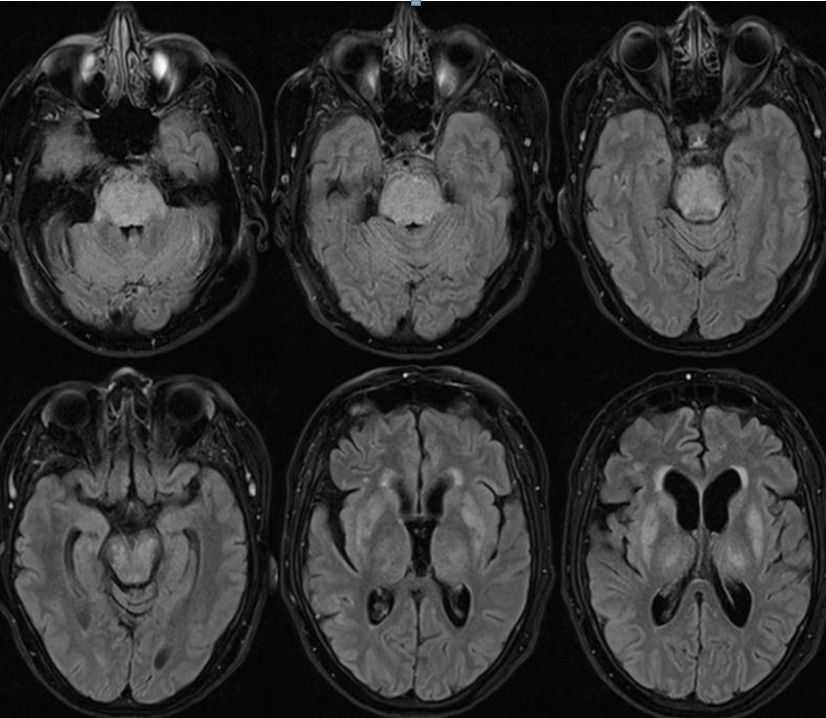

患者,女,27岁。发作性四肢抽搐20余天,精神行为异常10天入院。查体:颈抵抗(+++)。

答案:抗NMDA受体脑炎

这个患者的影像很有特点,皮层花边征,好多老师首先考虑到MELAS,但是患者颈部抵抗、左侧柔脑膜有强化等不好解释。影像表现为皮层花边征的同影异病有MELAS、自身免疫性脑炎、CJD等,一般来说,自身免疫性脑炎相对MELAS局限。患者青年女性,癫痫发作,精神行为异常应想到抗NMDA受体脑炎。抗NMDA受体脑炎儿童青年多见,女性多于男性。急性起病,可有发热,头痛等前驱症状。主要临床表现为精神行为异常,癫痫发作,近记忆力下降,言语障碍,运动障碍,不自主运动,意识水平下降,甚至昏迷等。头MRI可出现散在的皮层、皮层下点片状FLAIR及T2高信号,边缘系统病灶。